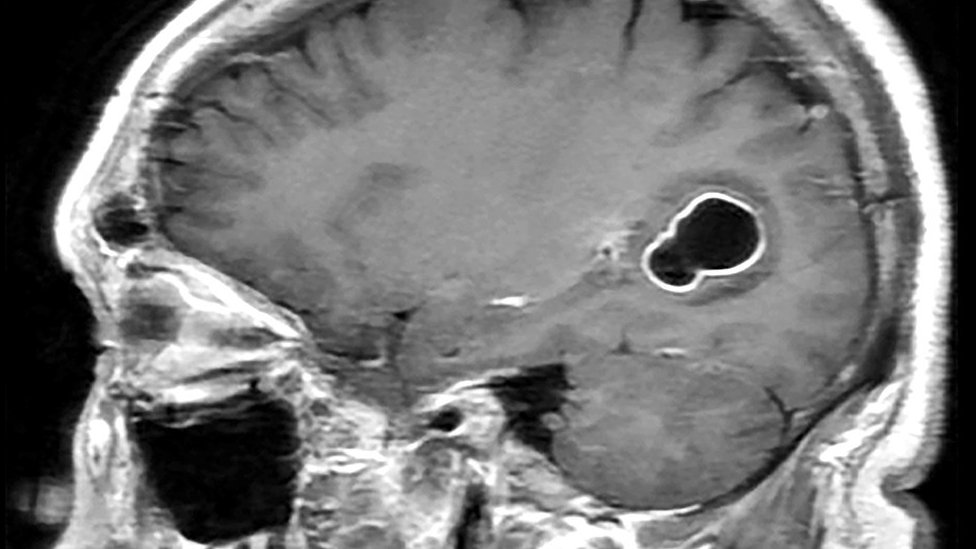

Skeniranjem glave otkrivene su larve pantljičare u njegovom mozgu koje izazivaju cisticerkozu.

Cisticerkoza je vrsta infekcije koju izazivaju larve parazita Taenija solijum, poznatog i kao svinjska trakavica (pantljičara), koja može dovesti do razvoja cista (cisticerka) u mozgu.

Prema Američkom centru za kontrolu i prevenciju bolesti, larve pantljičare dolaze do mišića i mozga i formiraju ciste.

Kada se ciste pronađu u mozgu, stanje se naziva neurocisticerkoza.